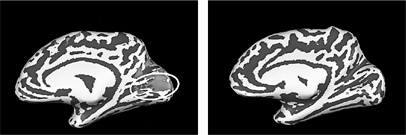

Для получения корректных результатов ученые удалили из общей картины эффекты воздействия на BOLD-сигнал собственных щелчков испытуемых, чтобы эти эффекты не мешали наблюдать за нейронной реакцией. В мозге зрячих участников не обнаружилось практически никакой дополнительной активности. Как и ожидалось, они слышали лишь собственные щелчки – и ничего больше. А вот результаты группы слепых, напротив, поражали. Когда они слышали запись щелчков собственного языка, МРТ фиксировал активацию зрительной коры.

Иллюстрация к книге — НейроЛогика. Чем объясняются странные поступки, которые мы совершаем неожиданно для себя [i_008.jpg]

Они не просто слышали эхо от щелчков. Их мозг анализировал эти звуки и составлял на их основе визуально-пространственную карту окружающей обстановки.

Хотя слепые ничего не видят, они не прекращают пользоваться затылочной долей мозга. Назначение зрения – помогать нам перемещаться в пространстве, а значит, выживать. Даже если зрительная информация больше не поступает, затылочная доля не перестает быть нашим компасом – она внимательно обрабатывает сведения о пространстве, которые черпает из других источников. Мозг строит картину мира путем соединения любых доступных фрагментов информации, даже если для этого приходится стирать границы между разными видами чувств, не только слухом и зрением.